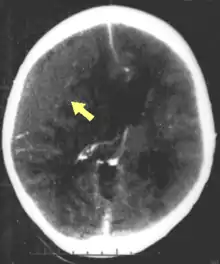

Hematomas, also focal lesions, are collections of blood in or around the brain that can result from hemorrhage.[10] Intracerebral hemorrhage, with bleeding in the brain tissue itself, is an intra-axial lesion. Extra-axial lesions include epidural hematoma, subdural hematoma, subarachnoid hemorrhage, and intraventricular hemorrhage.[38] Epidural hematoma involves bleeding into the area between the skull and the dura mater, the outermost of the three membranes surrounding the brain.[10] In subdural hematoma, bleeding occurs between the dura and the arachnoid mater.[22] Subarachnoid hemorrhage involves bleeding into the space between the arachnoid membrane and the pia mater.[22] Intraventricular hemorrhage occurs when there is bleeding in the ventricles.[38]

Movement disorders that may develop after TBI include tremor, ataxia (uncoordinated muscle movements), spasticity (muscle contractions are overactive), myoclonus (shock-like contractions of muscles), and loss of movement range and control (in particular with a loss of movement repertoire).[89][147] The risk of post-traumatic seizures increases with severity of trauma (image at right) and is particularly elevated with certain types of brain trauma such as cerebral contusions or hematomas.[138] People with early seizures, those occurring within a week of injury, have an increased risk of post-traumatic epilepsy (recurrent seizures occurring more than a week after the initial trauma).[148] People may lose or experience altered vision, hearing, or smell.[10]